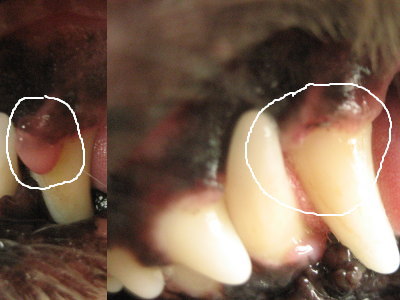

| 10月24日(月) 朝、ジジが柿を持ってやって来た。昨日、兄が採ってきたらしい。またみんなで食べよう♪ 首の痛みは、昨日の夜に首にシップを貼って寝たら少しマシに。いよいよ今日はアトムの腫瘍切除と歯石取りの日。アトムは朝ご飯抜きなので、私も付き合って朝ご飯抜き。(苦笑) 水分抜きは3時間前から。12時前に病院に連れて行く。鎮静を打ち、しばらく待っていよいよ注射。それでお預けです。4時過ぎたらお迎え可能・・・って事だけど、遅いほうが覚めもいいって言われたので、4時半頃に行く事にして、旦那に聞いたら、仕事を抜けて一緒に行く事になった。病院では歩いて出て来たけど、ヨレヨレ。(^_^;) アトムは旦那に任せて説明を聞く。歯はまだまだしっかりしてるとの事。腫瘍は2箇所切除。まだ他にも腫瘍になりそうな箇所があったみたい。でも、今回の大きさだと特に支障はなかったんじゃないか・・・との事。今後も経過観察かな。ただ肝臓の数値がまた上がってた(T_T)ので、薬再開。帰りは旦那に運転して貰って、アトムを抱っこして帰宅。最初は情けな〜い顔してたけど、家に近づくにつれ口が開いてきた。(笑) 家に帰ってもしばらくは寝付けないようだったけど、そのうち寝始めたのでやれやれ。6時には水と少しの食べ物解禁。でも9時過ぎに外に連れ出すまで、あまりに元気がなくて心配したけど、外に出た後ちょっと元気が出て来たよう。ミルクを飲ませて、食欲がありそうだったので、レトルトのささみを食べさせた。明日になったら元気復活するかなぁ〜。旦那宿直。 |